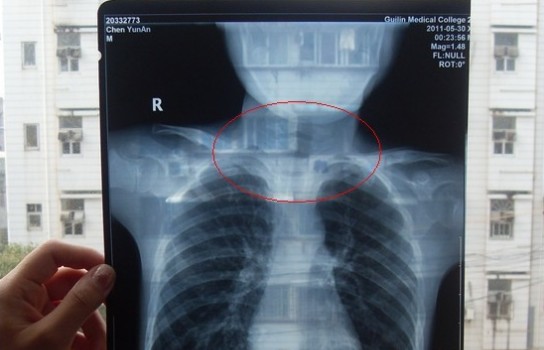

胸部正位X光片圖

2011年5月29日下午,陳先生的兒子安安出現嘔吐、肚子疼痛等癥狀。陳先生立即將兒子送往醫學院附院,根據醫生開出的會診單,分別對安安做了腹部立臥位2次和胸部正位1次共3次X光片檢查、診斷。醫生看X光片后排除了腸梗阻病因,判斷是闌尾炎。經過治療,不久安安身體痊愈。

可是,陳先生的一次偶然發現,讓他們一家過上了提心吊膽的日子。因為,在安安出院一個月后,陳先生偶然翻出孩子治療期間的X光片。發現在X光片中,孩子的生殖器官以及甲狀腺等敏感部位也在被放射區域中。而陳先生上網查到:人體拍攝X光片是有一定輻射的,并且輻射有可能引起基因變異等問題,他立馬陷入恐慌中。

至于,為什么拍攝X光時,孩子的敏感部位也在放射區域內,這讓陳先生百思不得其解。為此,他專門到醫學院進行了質疑。而醫院的醫務人員說,拍腹部X光片就要照到睪丸,要檢查睪丸是否正常,而且怕小孩亂動,所以要照寬些。